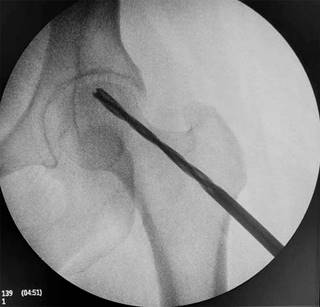

La técnica quirúrgica utilizada fue la perforación o Forage del núcleo cefálico, sobre mesa ortopédica bajo intensificador de imágenes (imagen en dos planos). Se introdujo una aguja guía hasta la zona de osteonecrosis. El orificio de inicio sobre la cortical externa del fémur se realizó a nivel del trocánter menor para evitar fracturas por estrés del fémur. A través de la aguja guía se introdujo una broca canulada de 9 mm de diámetro hasta llegar a 5 mm del cartílago articular (Figura 3). En todos los casos se obtuvo una muestra ósea para biopsia que confirmó el diagnóstico. Para la suplementación con ACMO, se obtuvo la muestra de zona dadora -cresta ilíaca- en forma percutánea, para posterior filtrado con utilización del sistema RegenKit BMC, Stryker, USA (Figuras 4 y 5).

Figura 3: Fresado de canal de descompresión y colocación de suplemento de aspirado de médula ósea.